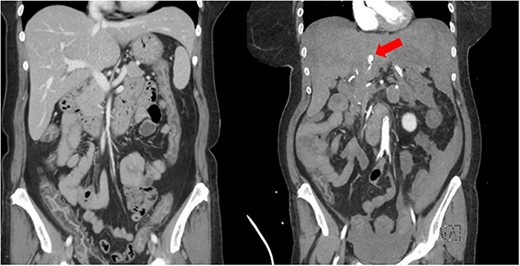

A 61-year-old female with a past medical history of hyperlipidemia, hypertension and diabetes presented to a referring facility emergency department with abdominal pain, nausea, vomiting, diarrhea and headache for 2 days. The patient did not take anticoagulants or antiplatelet therapy. She had no history of trauma. A computed tomography (CT) scan with intravenous contrast was obtained, which demonstrated diffuse colonic wall thickening. Her initial laboratory findings were within normal limits, and she was ultimately discharged with a diagnosis of nonspecific colitis. Later that same evening, the patient represented to the referring facility emergency department with worsening of her abdominal pain. Shortly after arrival, she became obtunded, required intubation and had a significant decline in her hemodynamics. Laboratory analysis revealed a hemoglobin of 8.3 g/dL (15.9 g/dL at the time of primary evaluation), a lactic acid of 20 and a pH of 6.8. An emergency CT angiogram was obtained. This revealed large amounts of intra-abdominal fluid consistent with hemoperitoneum that was new from the previous scan. It also demonstrated an arterial enhancing 13 mm central left hepatic lesion that represented a hepatic pseudoaneurysm (Fig. 1). Blood product administration was initiated, and the patient was transferred to our facility for further management.

Imaging showing initial CT scan (left) and repeat CT angiogram (right) several hours later. Red arrow is identifying left HAP.